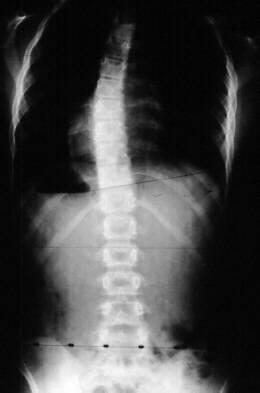

A 10 year old female presented with a spinal curvature which was first noted in a routine camp physical. She had no neurologic complaints. Her birth, medical, and developmental history were all unremarkable. Her family history was negative except there was a vague history of spinal curvature in the father. Physical examination was significant for a moderate left thoracic rib prominence, normal lower extremity reflexes, sensation and strength, but an absent abdominal reflexes in the upper and lower quadrants on the left side. A 24 degree left thoracic curve from T5 - Tl1 was measured (image 1). Also noted was an Arnold-Chiari malformation (image 2).